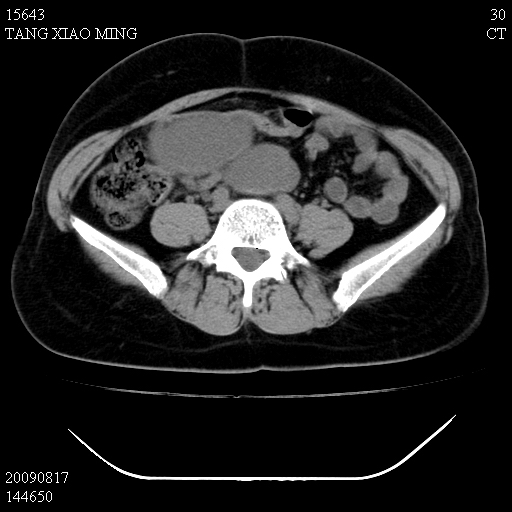

标题: CT21692:盆腔病变

女,33岁,右下腹痛2年余,既往宫外孕病史,如在我院手术,结果下周公布,

可能的诊断。1子宫内膜异位【子宫腺肌症并右卵巢巧克力囊肿】;2 右卵巢囊腺瘤。子宫肌瘤

1)考虑卵巢巧克力囊肿,不排除卵巢囊腺瘤。2)子宫肌瘤可能。

卵巢囊腺瘤,子宫肌瘤,直肠壁厚,不除外占位.